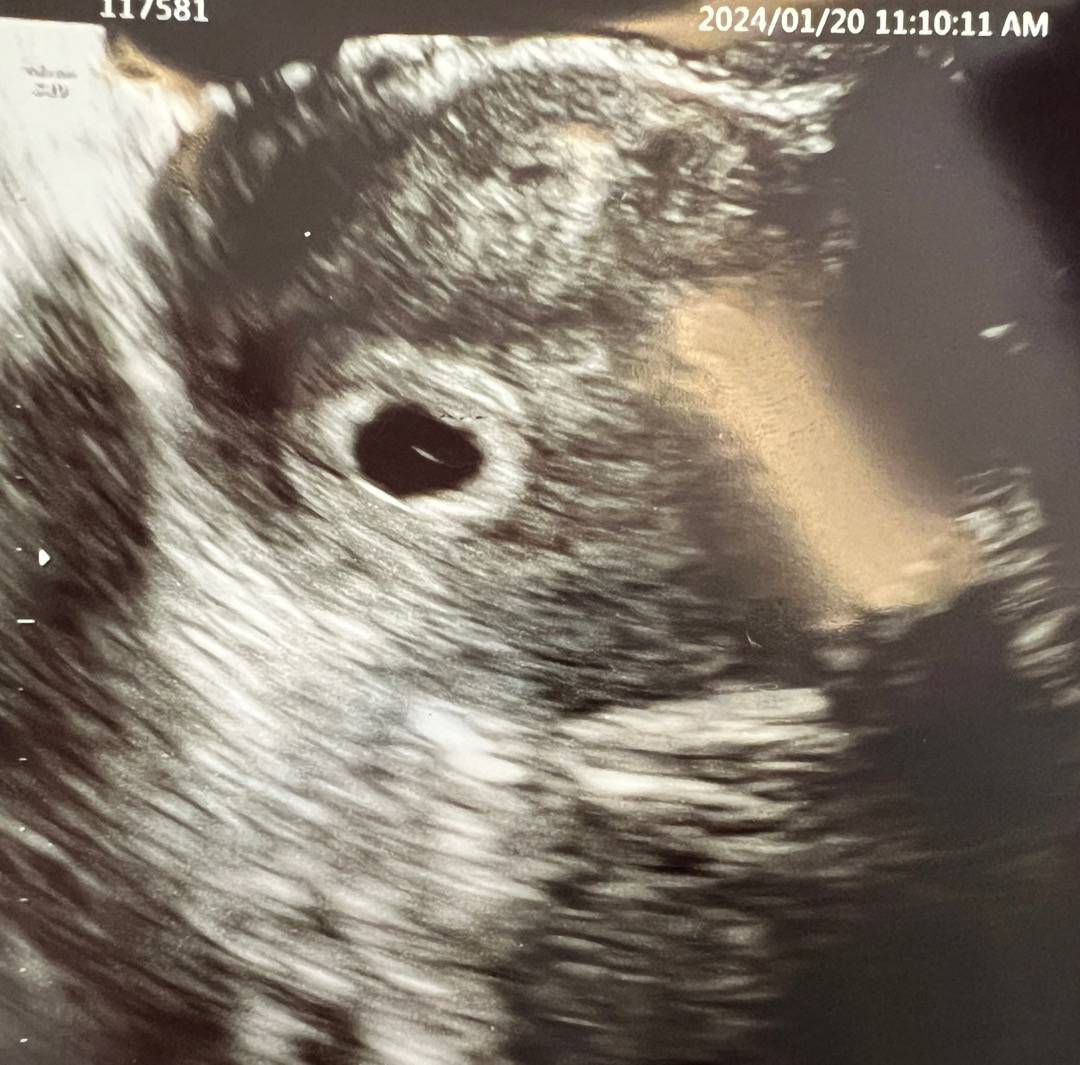

이거 난황이 맞나요~~?

6주0일차 같은데 애기집 안에 하얀게 난황이라고 하시던뎅.. 저렇게 납작하게 보이나요 ㅜㅜ? 링 같은 모양이 예쁘고 정상적인 난황 같은데 .. 엄청 좋았다가 걱정이 되네요^^;